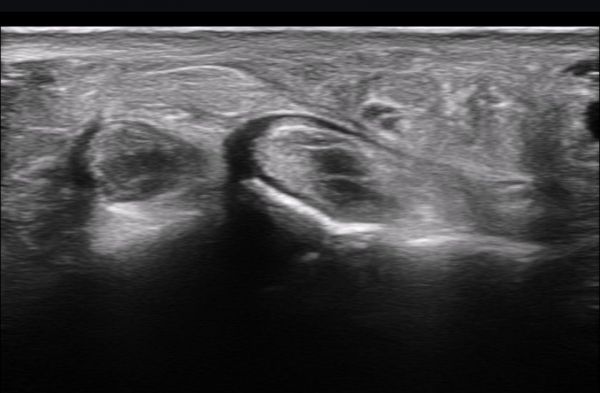

ÃÊÀ½ÆÄ ¼Ò°ß : ºñº¹½Å°æ Ⱦ´Ü¸é°Ë»ç¿¡¼­(»çÁø 1~13) ºñº¹½Å°æÀÇ Àú¿¡ÄÚ ºÎÁ¾°ú ´Üºñ°ñ°Ç³» ³¶Á¾¼º º´º¯ÀÌ °üÂûµÈ´Ù.

ºñº¹½Å°æ Á¾´Ü¸é°Ë»ç(»çÁø 14, 15)¿¡¼­ ºñº¹½Å°æÀÇ Àü¹ÝÀûÀÎ Àú¿¡ÄÚ ºÎÁ¾°ú ºñº¹½Å°æ ½ÉÃþÀ¸·Î ´Üºñ°ñ°Ç³»

³¶Á¾¼º º¯º¯ÀÌ °üÂûµÈ´Ù.